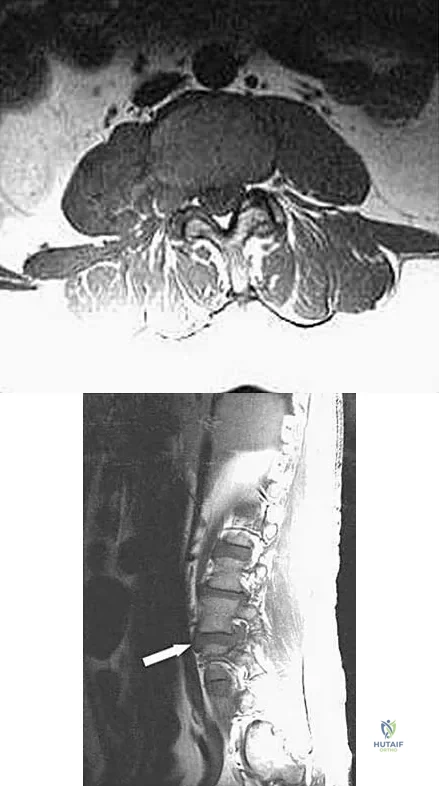

An otherwise healthy 45-year-old woman reports the onset of severe right leg pain. Figure 20a shows an axial MRI scan of the L4-5 level, and Figure 20b shows a sagittal view with the arrow at the L4-5 level. What nerve root is the most likely source of her pain?

Explanation